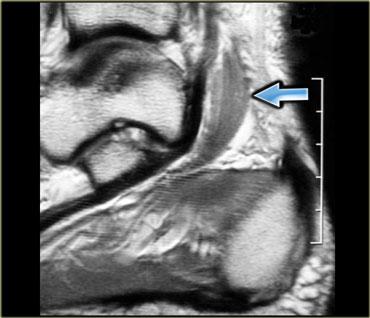

Cơ phụ có thể biểu hiện như một khối không triệu chứng, không đau, hoặc kèm theo các triệu chứng chèn ép thần kinh hay chèn ép mạch máu.

Hình bên trái minh họa một trường hợp cơ dép phụ ở mặt trong cổ chân, gây chèn ép thần kinh chày (tức hội chứng ống cổ chân).

Để chẩn đoán được thực thể này, người đọc cần phải thực sự thành thạo về giải phẫu của vùng đang khảo sát.

Bệnh nhân có cơ phụ thường đến khám với một khối không đau, thường được kỹ thuật viên đánh dấu vị trí.

Ban đầu, hình ảnh MRI có thể trông bình thường.

Tuy nhiên, cần lưu ý rằng có 3 câu hỏi cần cân nhắc trong các trường hợp này:

- Có lipoma dưới da không (rất dễ bỏ sót trên hình ảnh)

- Có mô xơ hoặc xơ u (fibromatosis) trên mạc cơ không (cũng rất dễ bỏ sót vì đây là mô tối trên nền mạc cơ)

- Có cơ phụ không